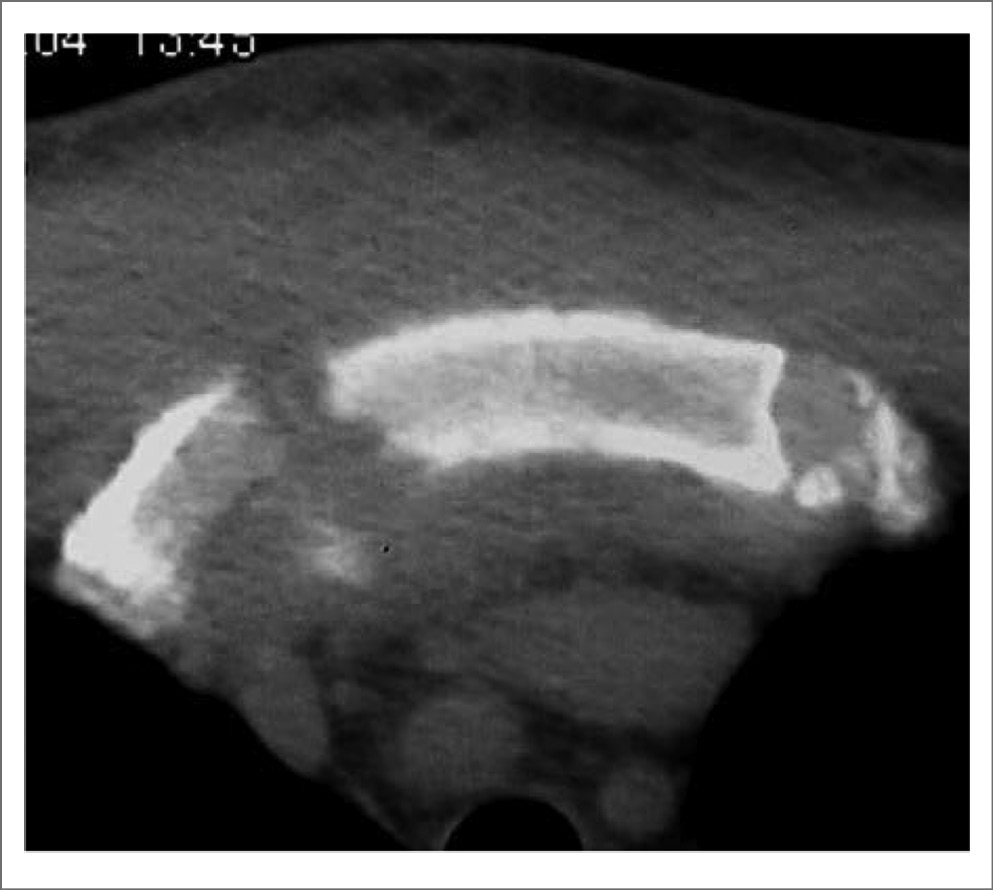

Поскольку в развитии ОАПГК существенную роль играет остеит, диагностическую ценность имеют рентгеновские методы, особенно компьютерная томография (КТ) [2, 17, 18]. Первоначально выявляются литические изменения медиального отдела ключицы и периостальное образование костной ткани, быстро формируется оссификация реберно-ключичной связки. Затем присоединяются признаки артропатии манубриостернального, грудино-ключичных и грудино-реберных суставов (эрозии и расширение, затем сужение щели, остеосклероз сочленяющихся отделов); рис. 4, 5. Очаговая деструкция грудины, ключиц, передних отрезков ребер, а также пролиферация костной ткани в виде периостита, гиперостоза костей, их неравномерного склероза напоминают картину остеомиелита.

Рис. 5. КТ области грудины (аксиальная плоскость) пациента Н., 39 лет, с ОАПГК (синдром SAPHO): деструкция сочленения между II правым ребром и грудиной, очаговая оссификация хряща сочленения между II левым ребром и грудиной, неравномерный остеосклероз и периостит тела грудины, выраженный отек мягких тканей кпереди от грудины (собственное наблюдение).